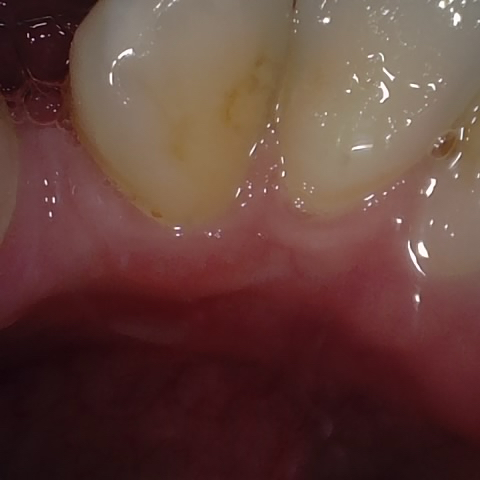

Image 63 / 400

NHD20738

Annotated as "Bad"

Original Image Rendering Image